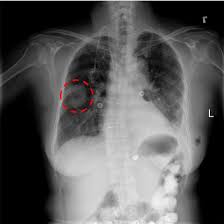

X rays are very helpful in the diagnosis of lung cancer in dogs. If you have lung cancer, it may be more difficult for your doctor to diagnose pneumonia. A white spot amidst the normal black lungs can therefore be a cancer, infection. Dog pneumonia or lung cancer. Pneumonia is a lung infection that leads to breathing difficulties and fluid in the lungs.

A definitive diagnosis of lung cancer requires a sample of tissue (biopsy). X rays are very helpful in the diagnosis of lung cancer in dogs. Primary lung cancer are frequently located in the caudal (towards the hind end of the pet) lung lobes, however can be located in any lung lobe and are usually a single mass in the lungs, unless the tumor has spread. If your dog has a chronic cough, you'll need to rule these out. The first of these possibilities could be investigated by bronchoscopy. A definitive diagnosis of lung cancer requires a sample of tissue (biopsy). The second kind of lung cancer in dogs is called metastatic lung cancer, which means the cancer originated somewhere else in the body, but has spread to the lung. Bacterial pneumonia is an inflammation of the lung usually caused by bacterial or viral infection but can be caused by inhalation of an irritant. The respiratory system consists of the large and small airways and the lungs. Lung cancer is actually the number one killer when it comes to cancers. But in some rare cases, it may be a lung cancer (primary or secondary). In both cases, you may have. Typical signs of bacterial pneumonia include fever, difficulty breathing, lethargy and coughing.

Primary lung cancer are frequently located in the caudal (towards the hind end of the pet) lung lobes, however can be located in any lung lobe and are usually a single mass in the lungs, unless the tumor has spread. My dog had pneumonia come on quickly this last august, we took her to the local er at 3am when we noticed her breathing labored and strange behavior. A white spot amidst the normal black lungs can therefore be a cancer, infection. Signs of the primary tumors in dogs. I haven't touched cigarettes a day in my life. Lung cancer often misdiagnosed as pneumonia urges requests for second medical opinions. Lung cancer is actually the number one killer when it comes to cancers. A definitive diagnosis of lung cancer requires a sample of tissue (biopsy). His appetite is basically normal though his blood work shows that he is anemic. 3 doctors agree send thanks to the doctor Other common respiratory diseases that might make you worried about cancer are …. Malignant tumors trigger inflammation in surrounding normal lung tissue, and they may obstruct. Pneumonia and lung cancer both affect the lungs but one is easily treatable and the other is potentially life threatening.

Deep Convolutional Neural Network With Transfer Learning For Detecting Pneumonia On Chest X Rays Springerlink from media.springernature.com Often, people with recurrent bouts of pneumonia tend to have unidentified lung cancer that can progress to advanced stages without appropriate treatment. A white spot amidst the normal black lungs can therefore be a cancer, infection. Here's why cancer can look like an infection: Persistent chest infections can be signs of something more serious than pneumonia, and unfortunately, it. A retrospective study of 1011 hospitalized patients with pneumonia was undertaken to assess the value of routine convalescent chest radiography for detection of underlying lung cancer. The first of these possibilities could be investigated by bronchoscopy. But the pneumonia density can obscure, or be distal to a cancer. Typical signs of bacterial pneumonia include fever, difficulty breathing, lethargy and coughing.